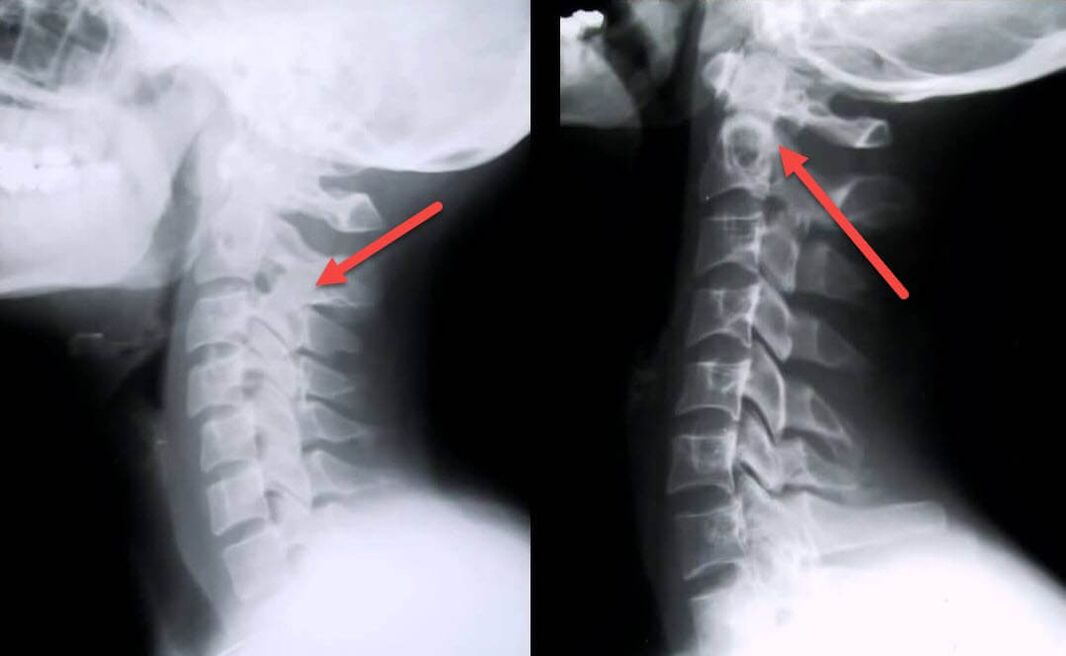

The most informative diagnostic procedure is radiography.Grade 1 pathologies correspond to radiological stage 1 or 2.The resulting images show the typical signs of the disease.

| X-ray stages of 1st degree cervical osteochondrosis | Characteristic signs |

|---|---|

| Section 1 | Minor changes in the curvature of the spine in the cervical region, affecting one or more segments |

| Section 2 | Slight thickening of intervertebral discs, deformation of uncinate processes, straightening of lordosis, minor growth of bone structures |